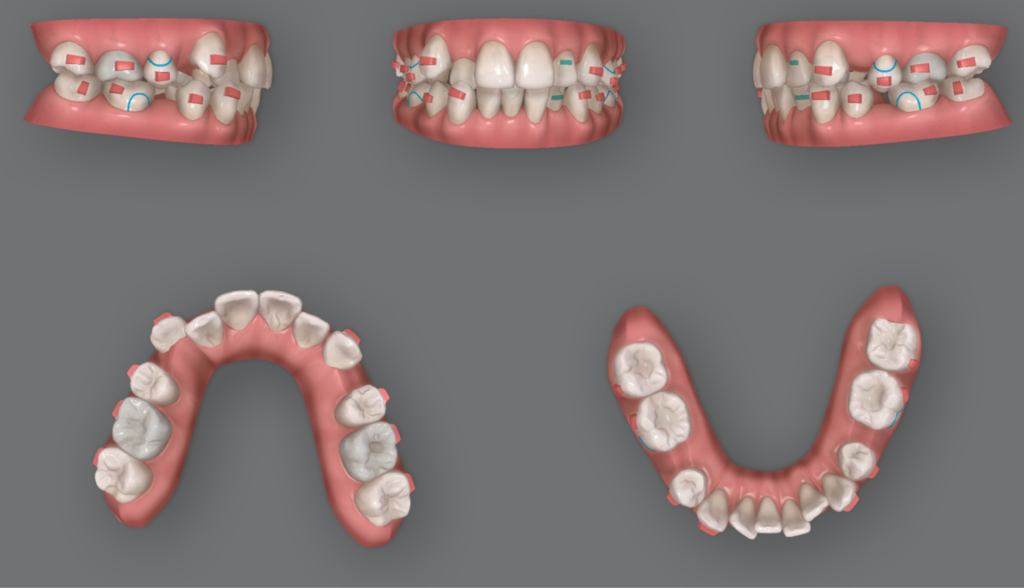

こちらのケースに関してもなるべく前歯を早く下げたいとの思いがあったことからIPRを併用し、治療期間の短縮を図りました。マウスピース矯正どこでやっても同じと言われがちですが、適切に診断し、治療短縮の工夫ができるか否かは、マウスピース矯正を担当する歯科医師の力量に左右されます。

通常であれば3年程度かかる重度の出っ歯のケースであっても、こちらのケースは1年半という短期間で終了することができました。